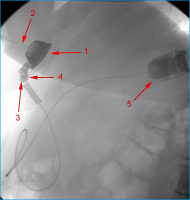

AGB

Abbildung 8: Bandleck nach AGB: Kontrastmittelinjektion in das Injektionsreservoir (1) mit wasserlöslichem, nichtionischem, isoosmolarem Kontrastmittel, über eine liegende Huber-Nadel (2). Der Katheter ist am Übergang zum Injektionsreservoir abgeknickt (3), wodurch es zu einem Kontrastmittelleck (4) kommt. Das Kontrastmittel der letzten Bandfüllung im Magenband (5) ließ sich am Beginn der Untersuchung nicht absaugen.

Keywords: GastroenterologieMagenbandRadiologie